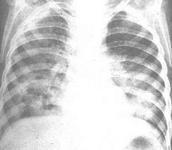

肺炎克雷白桿菌肺炎癥狀

• 肺炎克雷白桿菌肺炎

628健康網為您分享有關肺炎克雷白桿菌肺炎的癥狀,肺炎克雷白桿菌肺炎的治療方法,肺炎克雷白桿菌肺炎的預防知識,肺炎克雷...